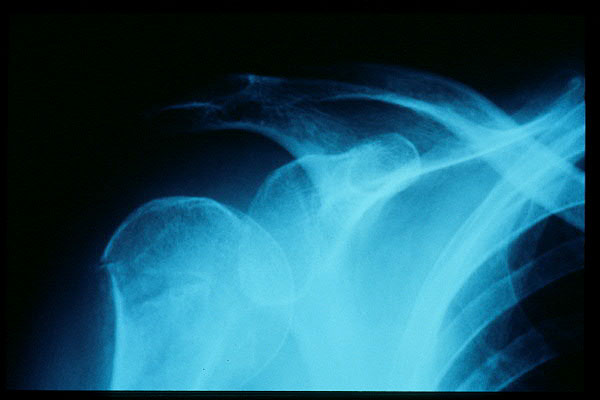

APR Luxación de hombro